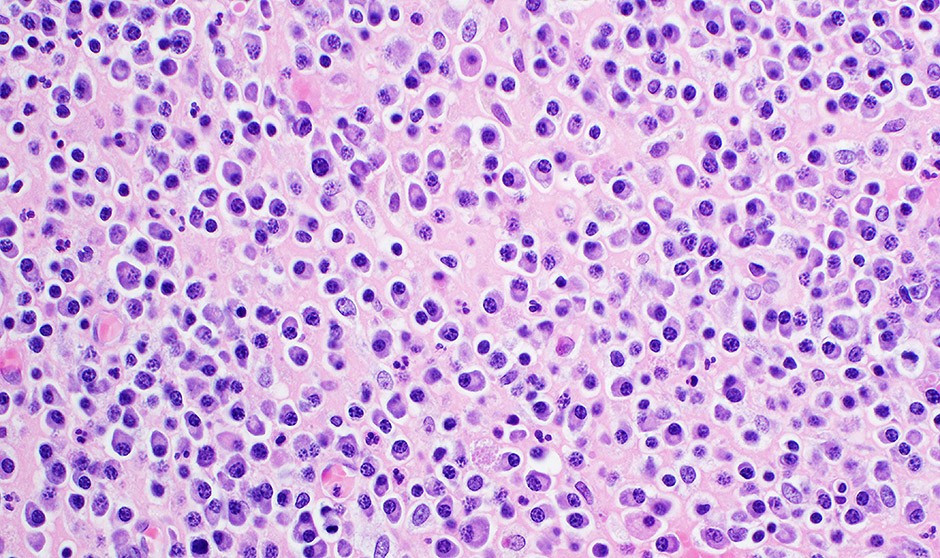

Micolactona, altamente tóxica para las células de mieloma múltiple

la micolactona es altamente tóxica para las células de mieloma múltiple, incluidas aquellas que se han vuelto resistentes a los inhibidores del proteasoma, en dosis que no son tóxicas para las células normales.

Además, demostraron que los inhibidores de la micolactona y del proteasoma funcionan en sinergia, potenciando mutuamente sus efectos anticancerígenos.